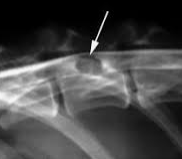

悪性骨腫瘍について悪性骨腫瘍のなかで、家畜に多発するものは骨肉腫(osteosarcoma)です。これには、造骨性骨肉腫(osteoplastic osteosarcoma)と軟骨肉腫(chondrosarcoma)があります。骨肉腫は壮老...